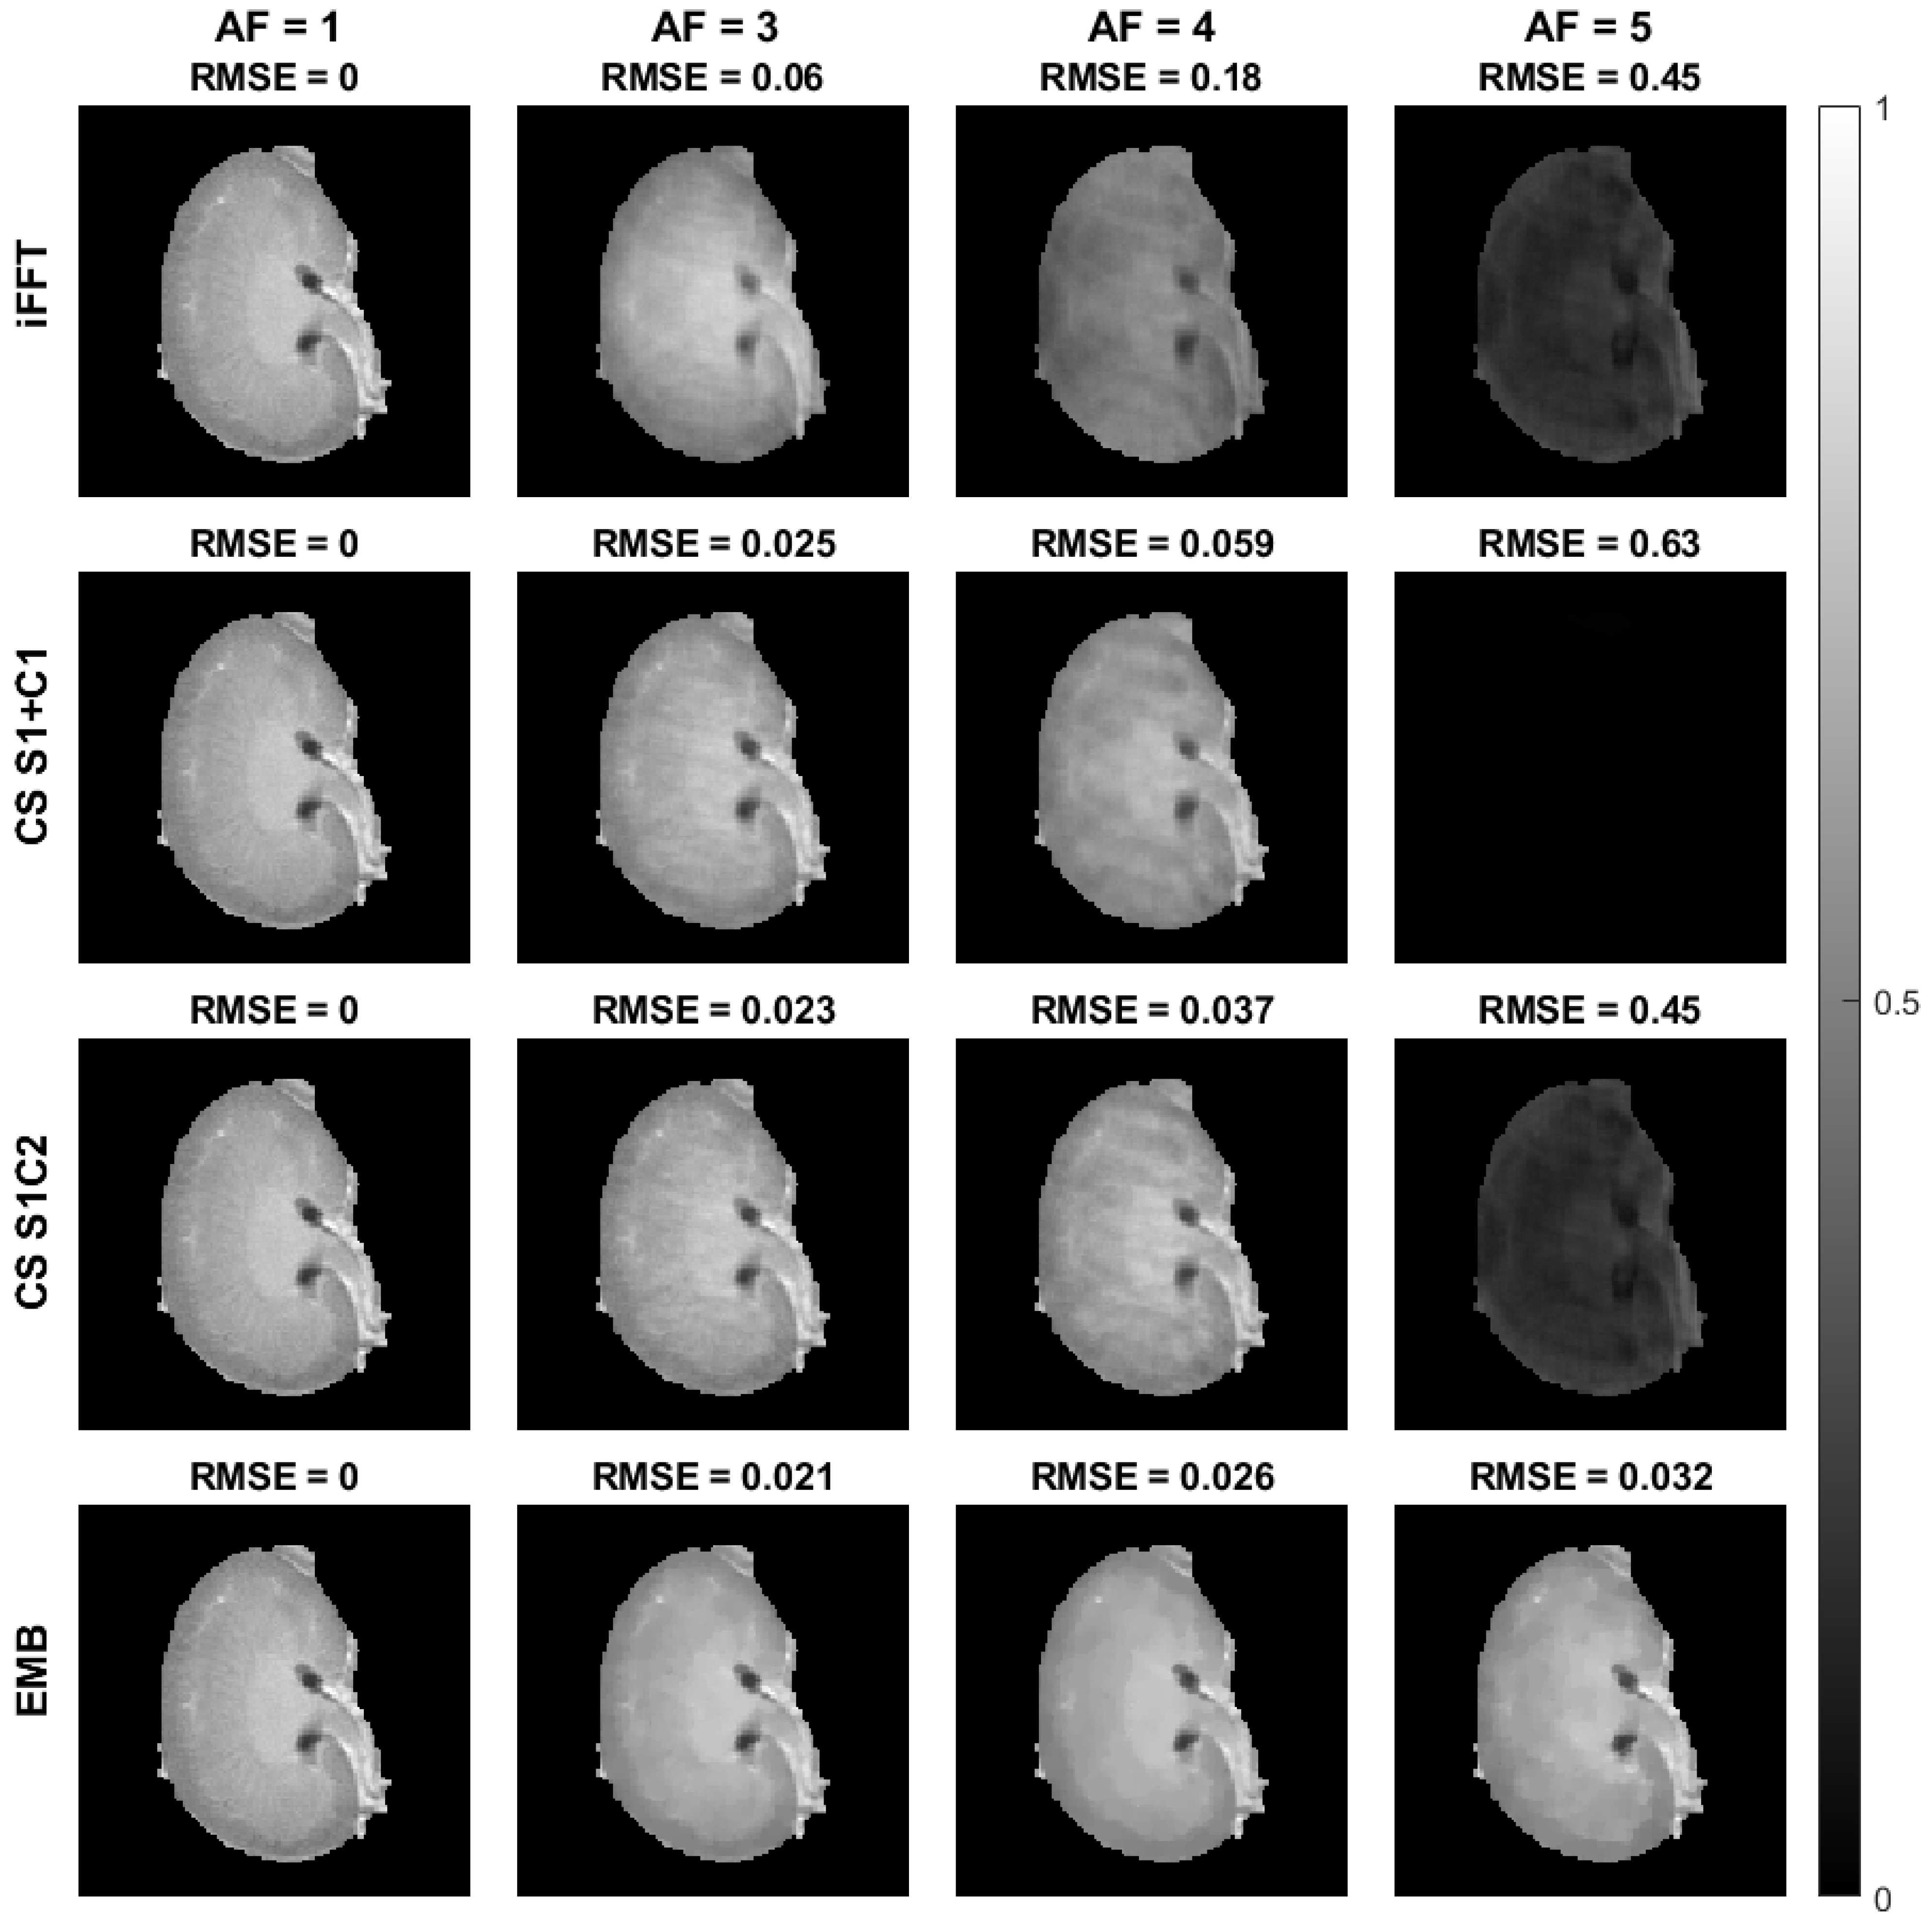

4.2. Cartesian Data from Ex Vivo Mouse Kidney